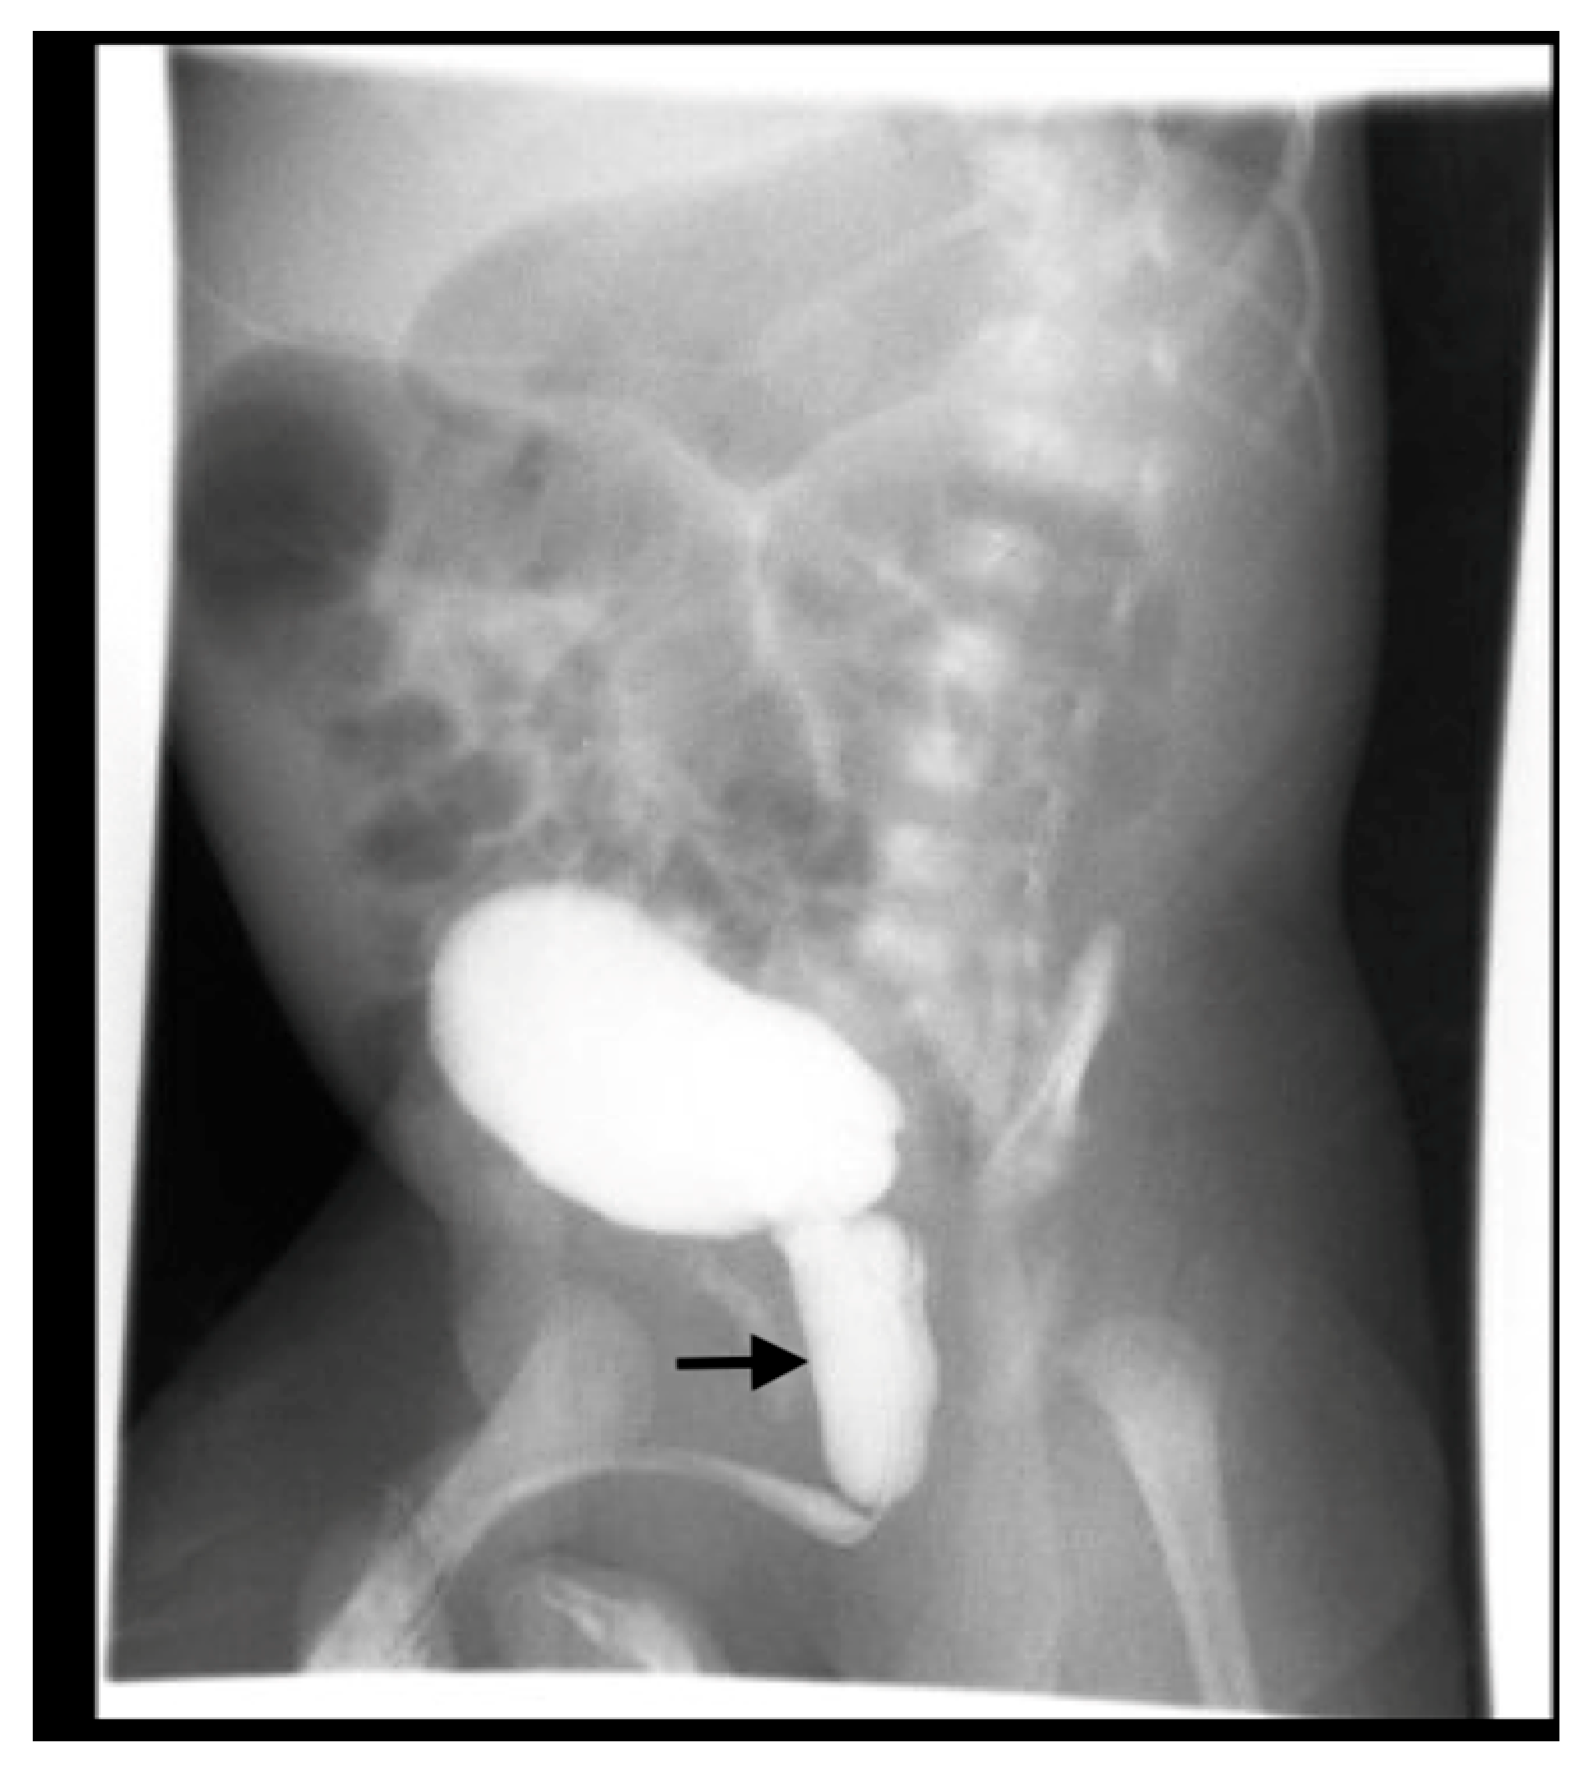

Bilateral hydronephrosis may also result from lower urinary tract obstruction, such as PUV. Fetal US can show a thick-walled, trabeculated bladder and a dilated prostatic urethra, which forms the characteristic “keyhole sign” in PUV. VCUG is the gold standard for diagnosing PUV (Figure 12).

Figure 12. Voiding cystourethrogram shows dilatation of the posterior urethra (arrow) in a 4-week-old boy with PUV.